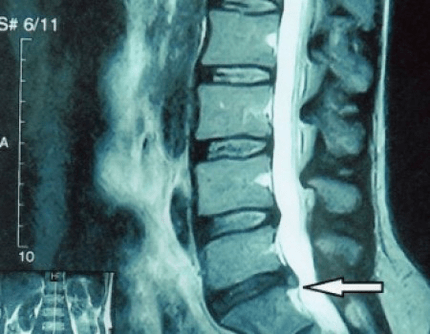

In typical cases, osteochondrosis of the cervical and cervical-thoracic spine occurs as described above.Therefore, the main stage of diagnosis was and remains the identification of the patient's complaints, establishing the presence of concomitant muscle spasm by simple palpation of the muscles along the spine.Is it possible to confirm the diagnosis of osteochondrosis by X-ray examination?

An “X-ray” of the cervical spine, and even with functional tests of flexion and extension, does not show cartilage, since its tissue transmitsand dehydrated.Functional testing can confirm the diagnosis of cervical spine instability.

Since the discs themselves can only be seen using CT or MRI, MRI and X-ray CT are indicated to clarify the internal structure of the cartilage and formations such as bulges and hernias.Thus, with the help of these methods, an accurate diagnosis is made and the result of the tomography is an indication, and even a topical guide, for the surgical treatment of a hernia in the neurosurgery department.